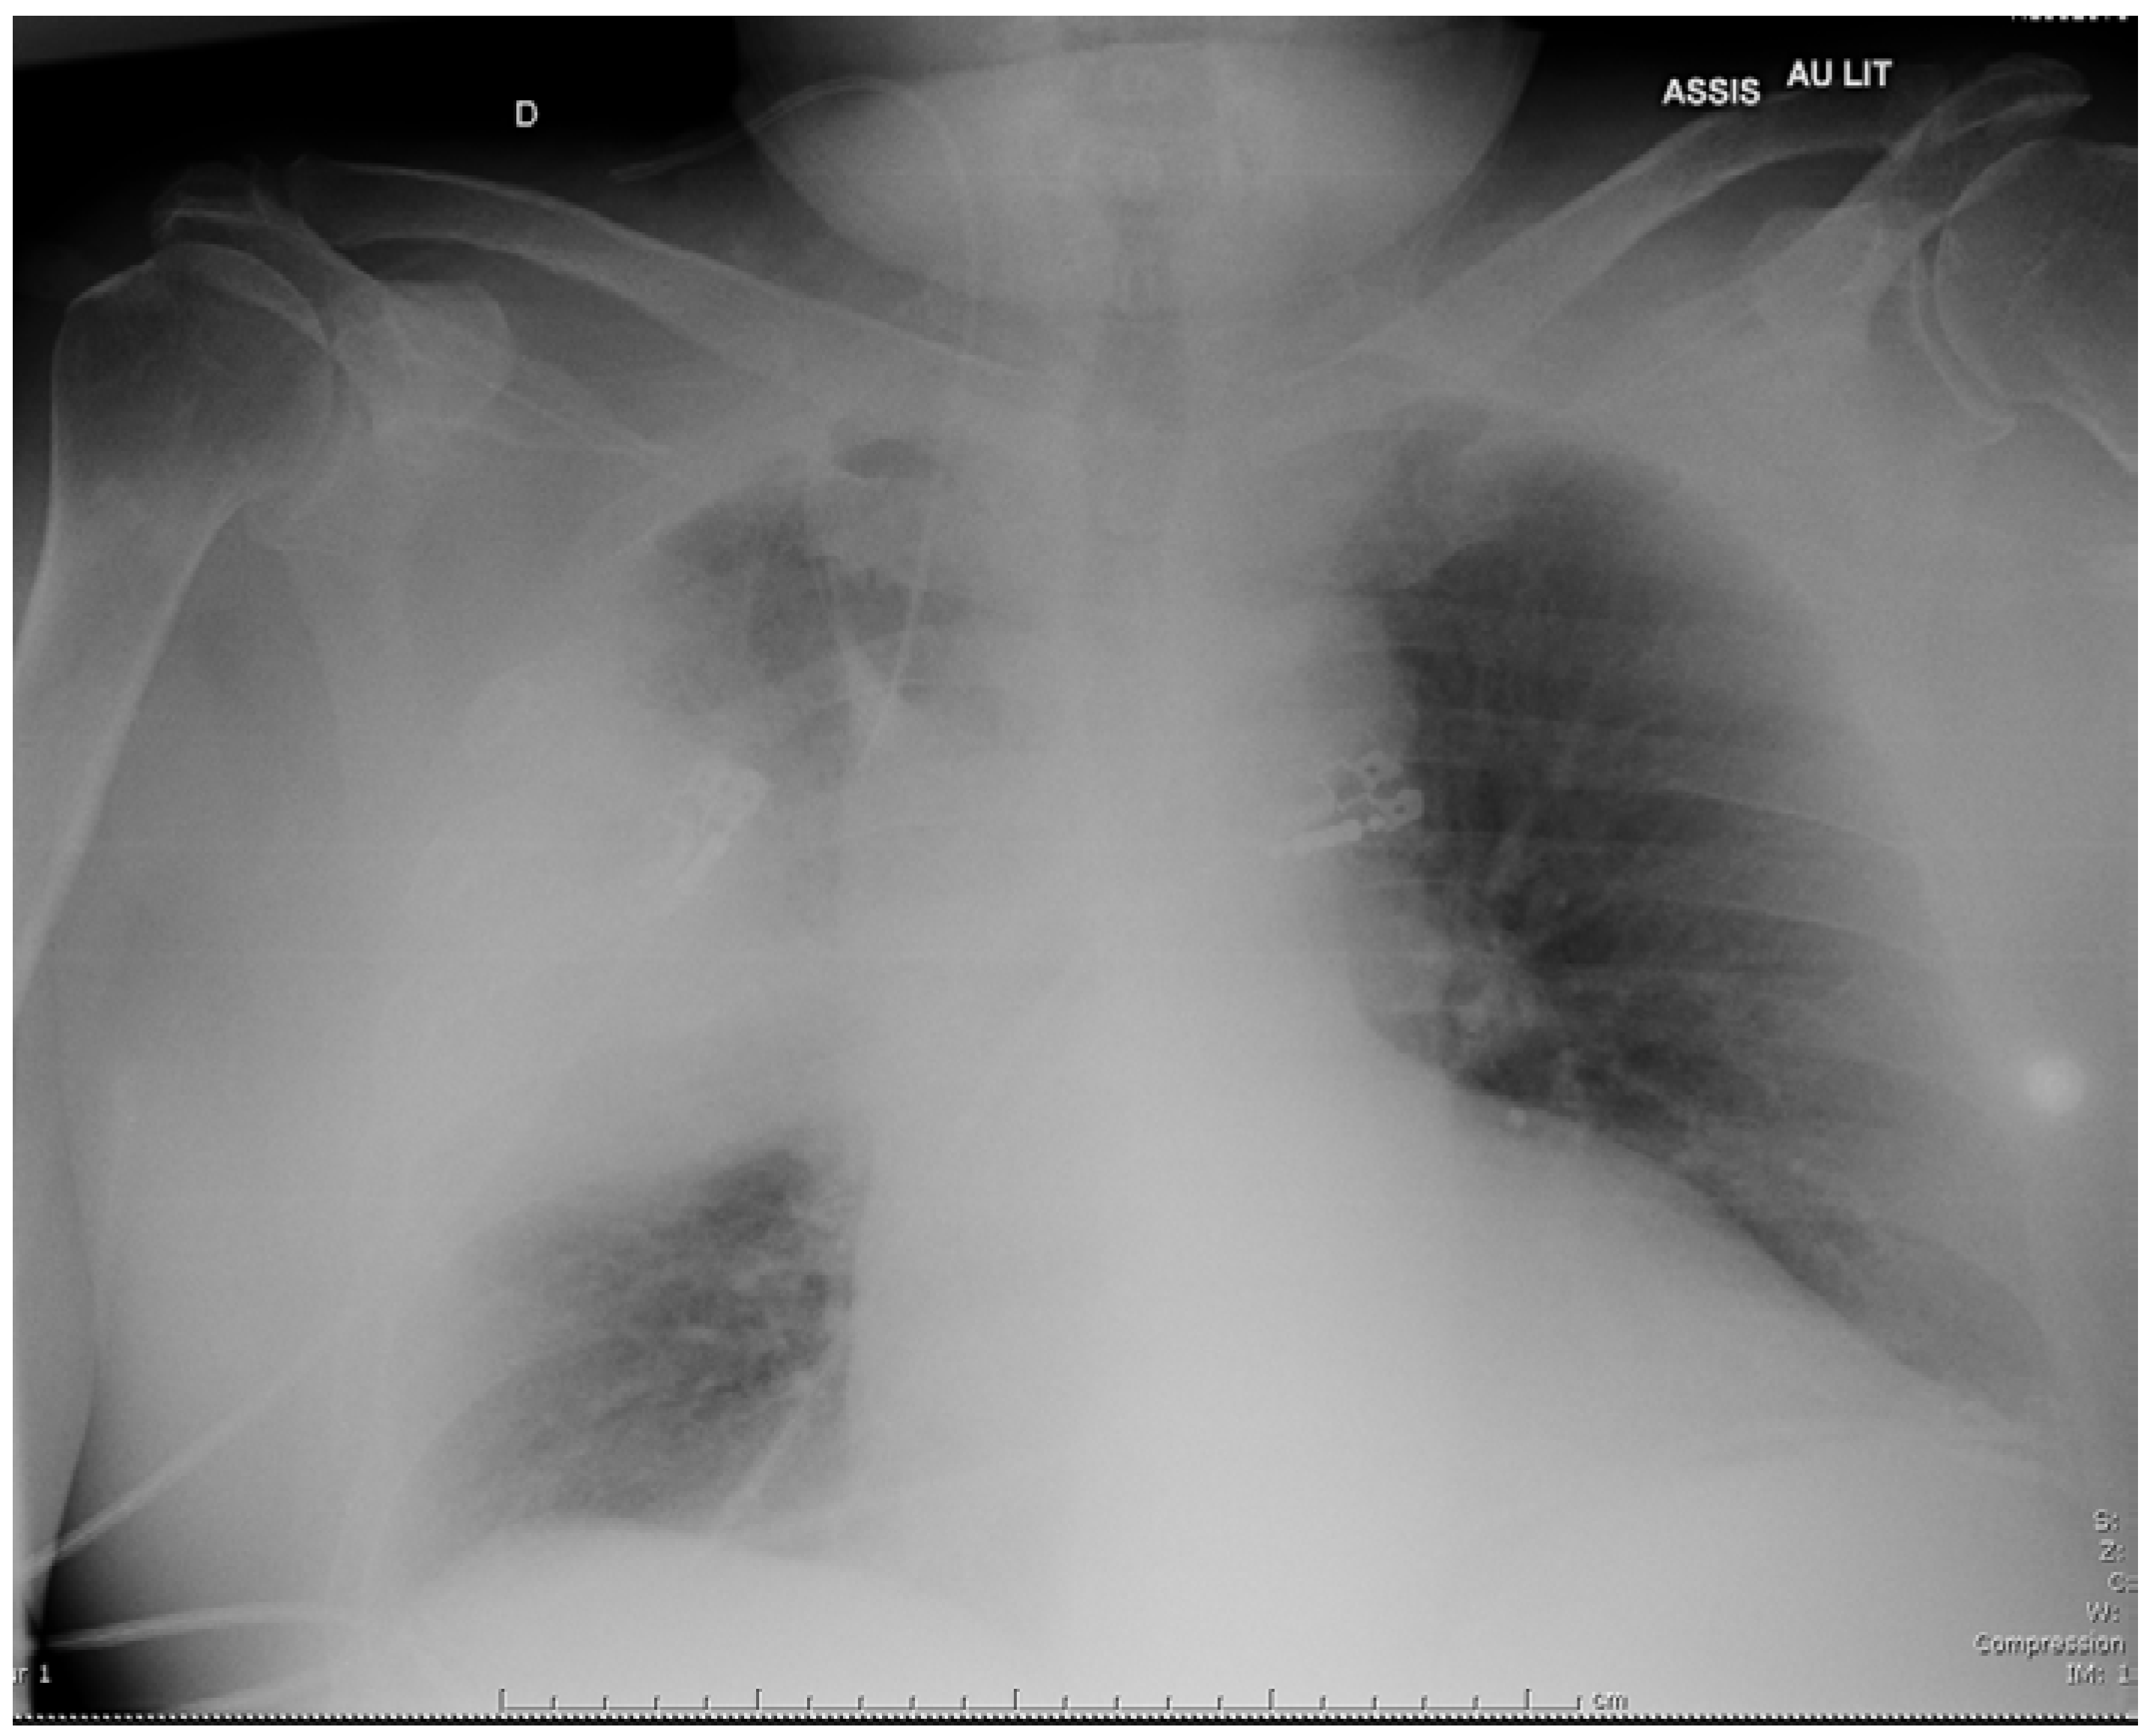

A 69-year-old man presented in November 2018 with a 3-day history of cough and fever. He reported significant tobacco consumption, type 2 diabetes, obstructive sleep apnea (OSA) and rheumatoid arthritis (RA) treated with successive tumor necrosis factor-alpha inhibitors since 2004. His immunosuppressive therapy had been strengthened with high-dose corticosteroids in August 2018 because the RA had relapsed, and etanercept had just been replaced by abatacept (an inhibitor of the cytotoxic T lymphocyte-associated antigen-4 receptors) few days prior to admission. The first evaluation revealed: temperature of 37.9 °C, blood pressure of 126/69 mmHg, respiratory rate of 32/min, and oxygen saturation of 95% on 3L/min of O2. He was alert but complained of cough and dyspnea. The chest examination mainly revealed crackles in the right field. Initial lab work showed: hemoglobin 12.8 g/dL, WBC count 9,600 /µL, platelet count 178,000 /µL, creatinine level 22.3 mg/L, C-reactive protein 514 mg/L, and procalcitonin 4.9 ng/mL. On room air arterial blood gas showed pH of 7.50, O2 pressure of 53 mmHg, and CO2 pressure of 34 mmHg. Chest X-ray demonstrated alveolar infiltrates in the middle part of the right lung (Figure 1). The patient received intravenous (i.v.) cefotaxime, 2 g every 8 h, plus i.v. levofloxacin, 500 mg daily, as empirical therapy, then was admitted to the intensive care unit because he required non-invasive ventilation.

Figure 1. Chest X-ray on admission showing a right consolidation in the right lung.